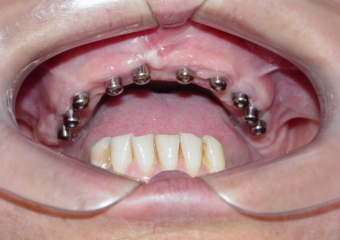

Implantes instalados com cicatrizadores